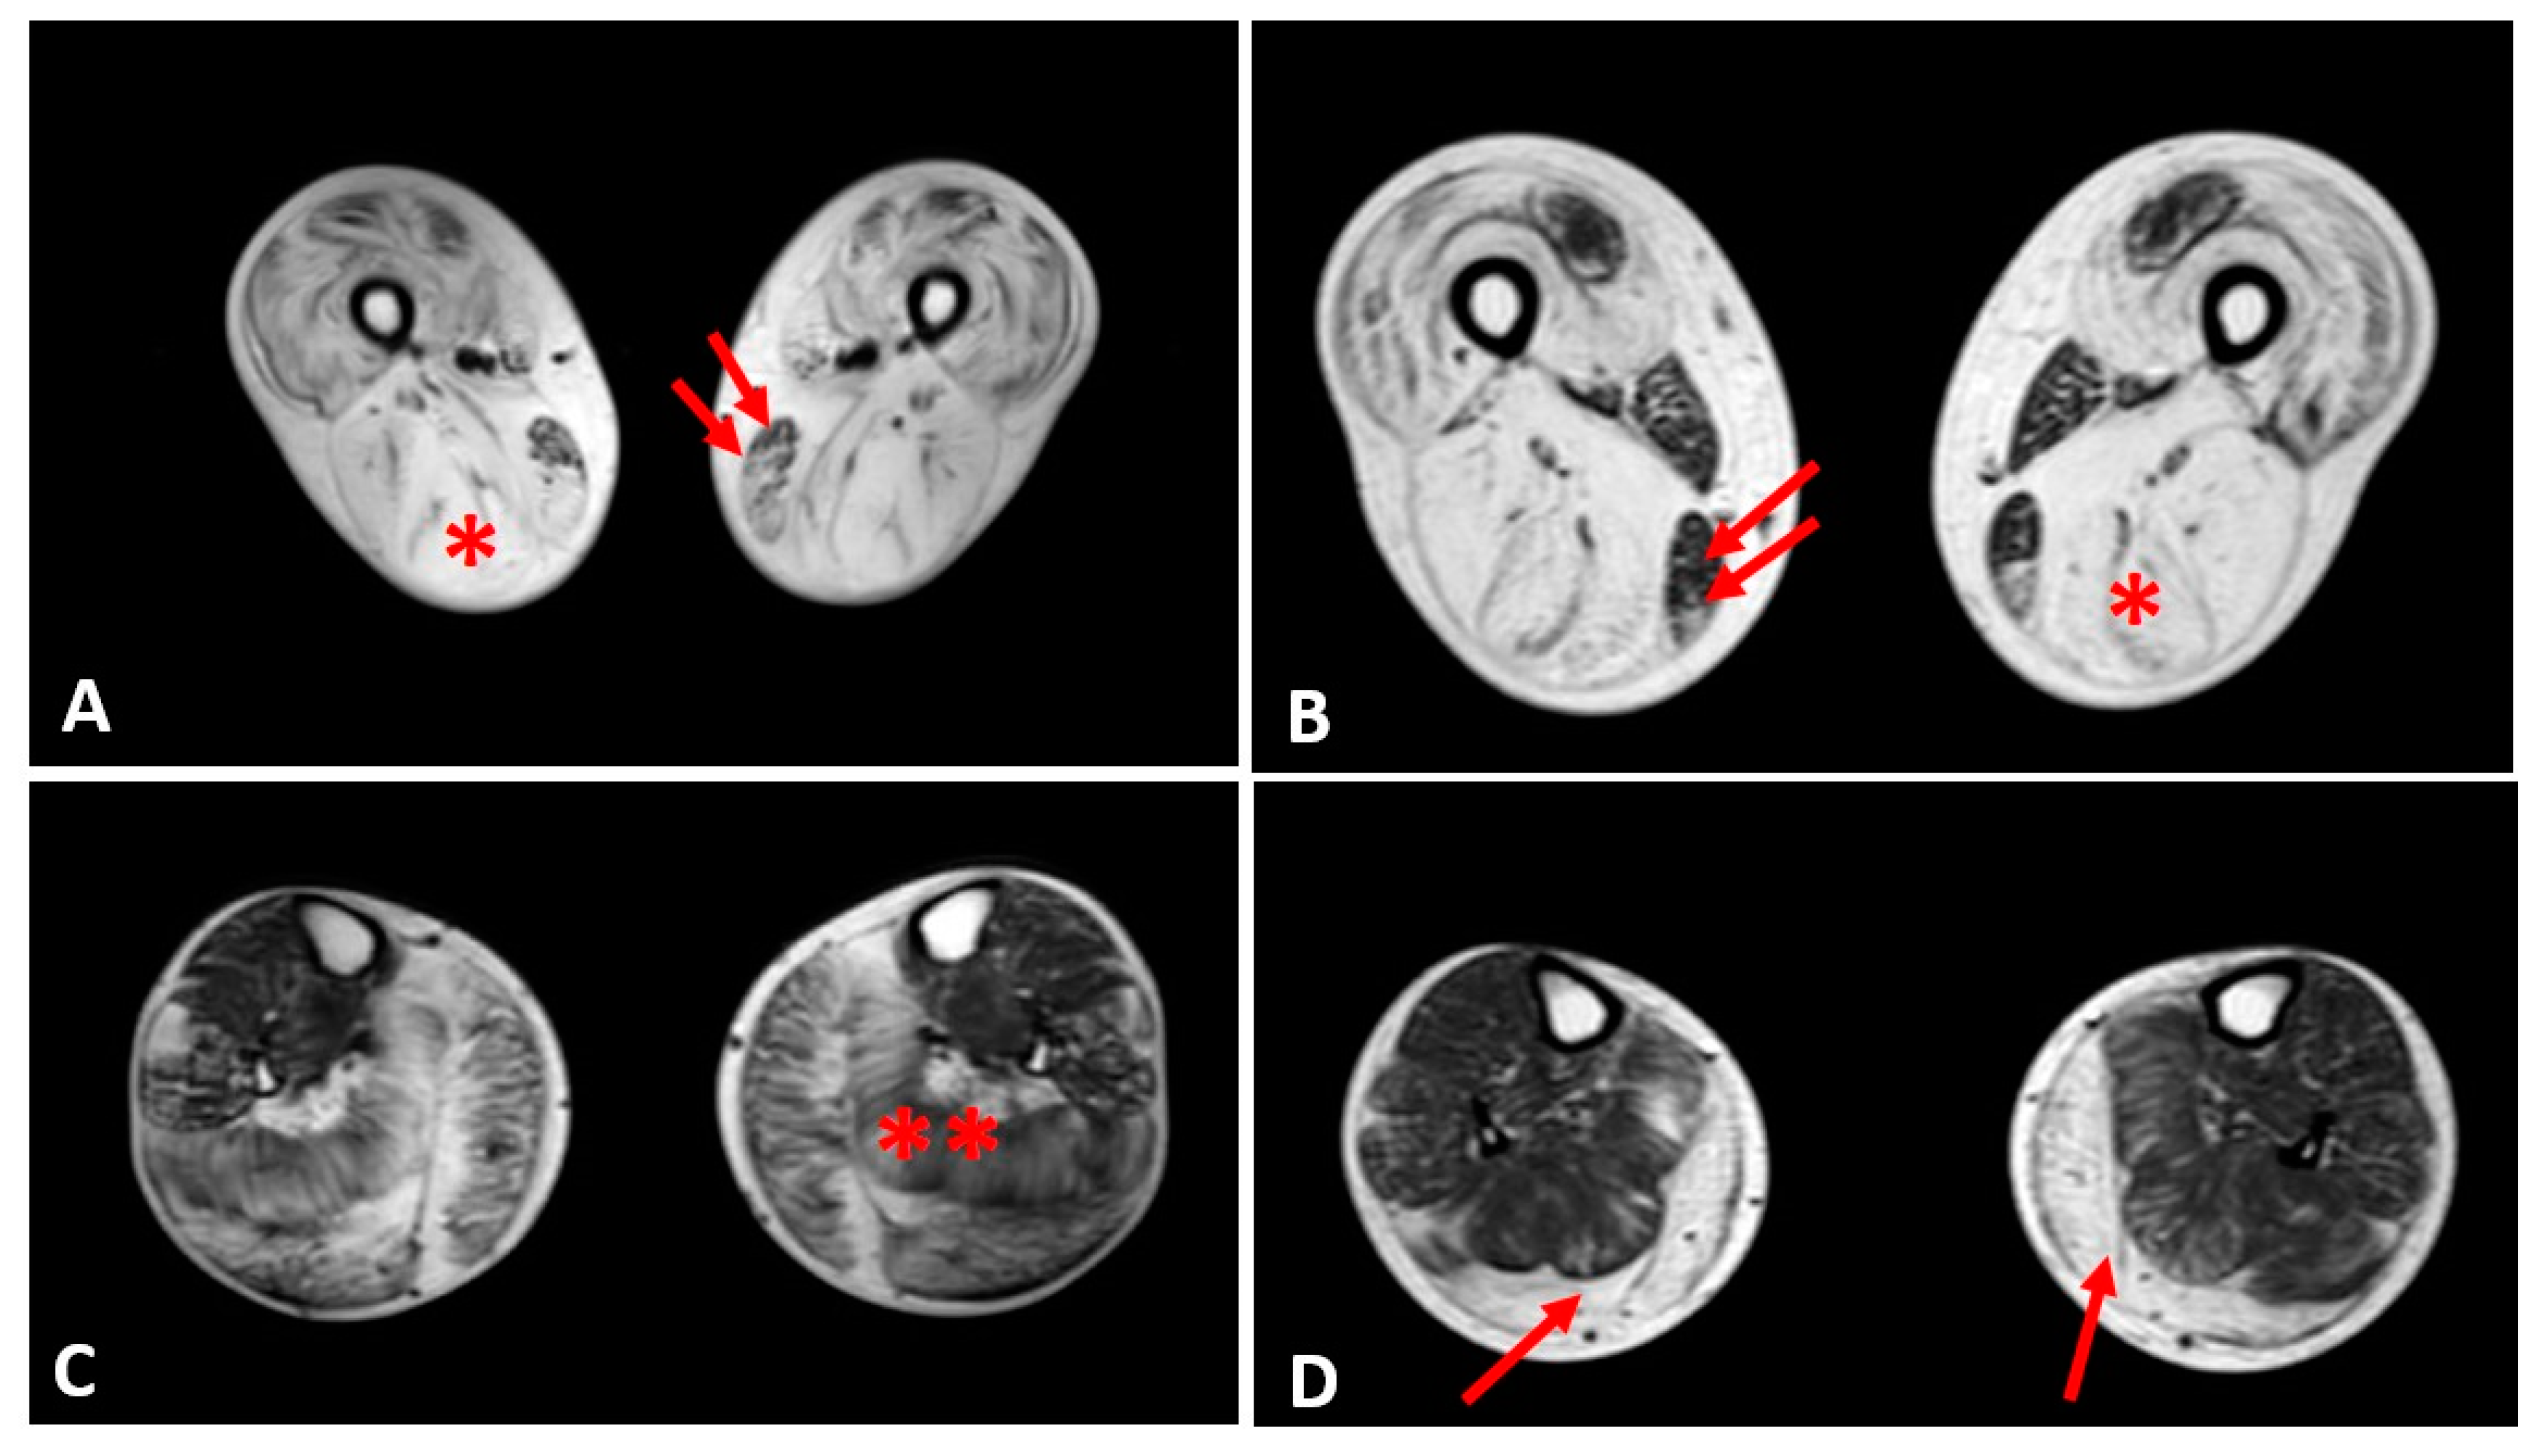

3.4. Muscle MRI Changes